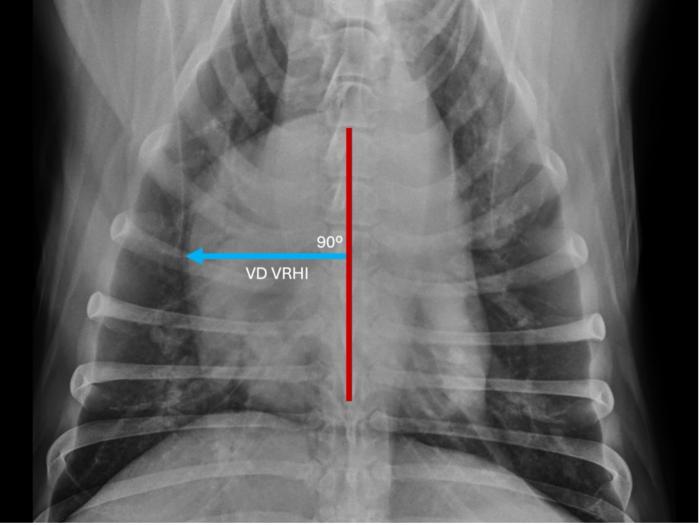

La determinación del VRHi se basó en el protocolo descrito por Puccinelli y colaboradores(2024). En la proyección LLD, el eje largo y el eje corto máximo de la silueta cardíaca se identificaron como se describió previamente para la escala cardíaco vertebral o índice de Buchanan (Buchanan & Bücheler, 1995). En el eje corto, se midió la distancia desde el margen craneal de la silueta cardíaca hasta la línea de intercepción del eje largo. Posteriormente, la misma línea se colocó sobre las vértebras torácicas comenzando en el borde craneal de la cuarta vértebra torácica, y se estimó el número de cuerpos vertebrales (CV). En la vista VD, el eje longitudinal torácico se trazó como una línea superpuesta a la columna vertebral. En el eje transversal, se calculó la distancia desde el margen derecho de la silueta cardíaca hasta el eje longitudinal torácico y se midió contra las vértebras torácicas en las vistas laterales, como se describió anteriormente (Figura 1 y 2).

Representación de la determinación del índice cardíaco vertebral derecho (VRHi) en proyección ventro-dorsal (VD) en un perro parasitado por Dirofilaria immitis y que sufría de hipertensión pulmonar. Valor de 2,5 cuerpos vertebrales al trasladar la determinación sobre las vértebras torácicas comenzando en el borde craneal de la cuarta vértebra torácica en proyección latero-lateral derecha (línea de color azul).